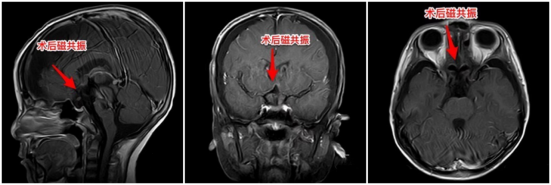

顺利切除颅咽管瘤后开始探索脑出血原因,见基底动脉主干上有一个灰白色可疑动脉瘤,其基底部动脉壁呈鲜红色,与聪聪刚起病时蛛网膜下腔出血位置吻合,断定这就是引起聪聪脑出血的“罪魁祸首”,经过评估考虑为血泡样动脉瘤。

术中,周忠清主任小心翼翼地用骨膜片围绕动脉瘤颈部,动脉瘤夹夹闭动脉瘤颈部,导致动脉瘤颈部断裂、脱落,用骨膜片包裹基底动脉,动脉瘤颈表面垫肌肉片,再用动脉瘤夹夹紧骨膜片,封闭基底动脉破口,达到加固基底动脉的效果,最后顺利切除动脉瘤。手术持续6小时,顺利完成,成功将聪聪脑子的“两个炸弹”同时拆掉。

术后行脑血管造影,显示基底动脉血流通畅,顺利度过恢复期,聪聪安全出院,出院前没有明显的神经功能障碍,行动自如,聪聪父母悬着的心终于落地。